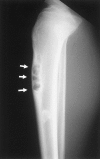

Fibrous dysplasia and osteofibrous dysplasia are both benign fibro-osseous lesions of the bone and are generally seen during childhood or adolescence. Histologically, the features of these bone lesions sometimes look quite similar, but their precise nature remains controversial. Mutation of the alpha subunit of signal-transducing G proteins (Gsalpha), with an increase in cyclic adenosine monophosphate (cAMP) formation, has been implicated in the development of multiple endocrinopathies of the Albright-McCune syndrome and in the development of fibrous dysplasia. We studied Gsalpha mutation at the Arg201. codon in seven cases of fibrous dysplasia (six monostotic lesions and one polyostotic lesion) and seven cases of osteofibrous dysplasia using formalin-fixed, paraffin-embedded tissue, by means of polymerase chain reaction-restriction fragment length polymorphism and direct sequencing analysis. All of the seven cases of fibrous dysplasia showed missense point mutations in Gsalpha at the Arg201 codon that resulted in Arg-to-His substitution in three cases and Arg-to-Cys substitution in four cases. On the other hand, the seven cases of osteofibrous dysplasia and the normal bone used as a control showed no such mutation. These data suggest that fibrous dysplasia and osteofibrous dysplasia have different pathogeneses and that the detection of Gsalpha mutation at the Arg201 codon is quite useful for distinguishing between these lesions.